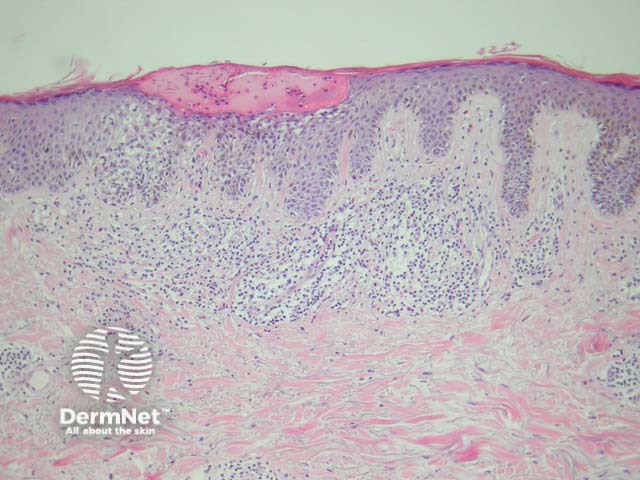

Compound melanocytic naevi have a central raised area with surrounding flat pigmentation. The epidermis may be normal in appearance, acanthotic or display seborrhoeic keratosis-like changes. Nests of melanocytes are found at the dermoepidermal junction and within the dermis. Melanocytes exhibit maturation as they become deeper and tend to be smaller with less pigmentation. (figures 2, 3).

Figure 2

Figure 3